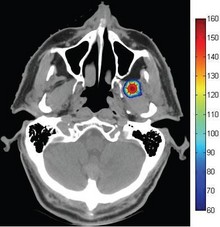

In recent years, optical manipulation using optical radiation pressure has been widely studied. In this study, the radiation pressure exerted on various kinds of microscopic objects with different laser beams was evaluated by COMSOL Multiphysics software. By changing beam shapes, ... Read More